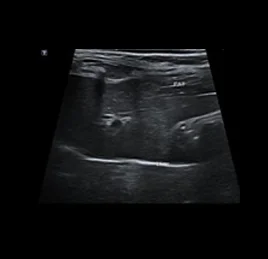

초음파 검사는 고주파 음파를 이용해 장기와 조직의 실시간 움직임을 영상으로 확인하는 비침습적 진단법입니다.

장기의 구조뿐 아니라 혈류, 운동성, 기능 변화까지 평가할 수 있어, 다양한 질환의 조기 발견과 모니터링에 효과적입니다.

• 지방간

• 담낭 점액종

• 비장 종양

• 수신증

• 만성 신부전

• 방광 결석

• 부신 종양

• 혈관 이상 - PSS

• 췌장염

• 췌장 농양

• 위장관염

• 소장 종양